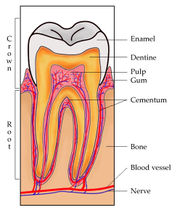

| 17. 6. 2011, 09:09 | Zub diagram.jpg (soubor) |  | 55 kB | Webmaster | 1 | |